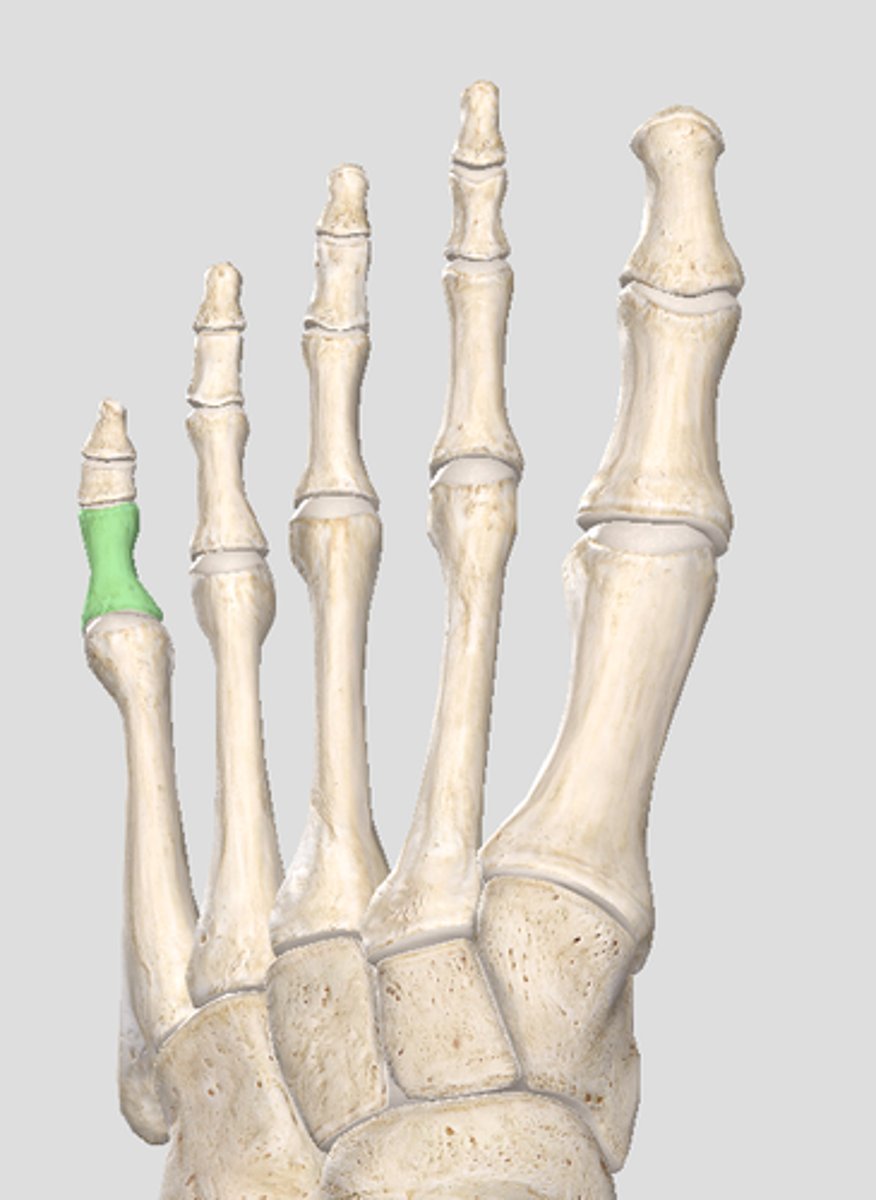

Proximal phalanx of digit 5

Middle phalanx of digit 5